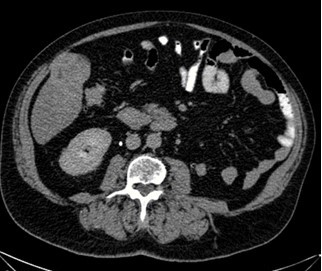

Reportamos el caso de un paciente masculino de 65 años de edad quien consultó por control. Con antecedente de carcinoma de células claras de riñón izquierdo estadio II ameritó nefrectomía radical izquierda y adenocarcinoma de próstata Gleason 9 avanzado oligometastásico, recibió tratamiento con bicalutimada, zoladex y abiraterona acompañado de radioterapia 39 ciclos; hábito OH acentuado, durante la consulta se le evidencia mediante ecografía abdominal lesión ocupante de espacio de segmento V hepático. Fue estudiado con tomografía con protocolo hepático donde se evidencia imagen redondeada de 4,7 cm, que presenta captación discreta heterogénea periférica en fase arterial, lo que sugiere área de necrosis central y un wash out lento en fase de eliminación, dicha lesión está ubicada en el segmento V y se encuentra en íntima relación con los músculos de la pared abdominal anterior ( Figura 1 y 2), Fibroscan en el cual no se evidencia cirrosis hepática, sin embargo, en vista del tamaño del tumor y antecedentes del paciente se decide realizar resonancia magnética nuclear (RMN), en la cual se evidencia lesión redondeada, bien delimitada, heterogénea que mide 5 cm x 4,5 cm x 4,2 cm en lóbulo hepático derecho segmento V con un volumen aproximado de 50 cm3 (Figura 3 y 4), pruebas de funcionalismo hepático alteradas AST 301U/l, ALT 206U/l, alfafetoproteína 244,10 ng/mL, antígeno carcinoembrionario 2,23 ng/mL, Ca 19-9 1,00 U/mL, con CT PET del año anterior negativo, por lo cual se decide realización de intervención quirúrgica con sospecha diagnóstica de carcinoma hepatocelular.